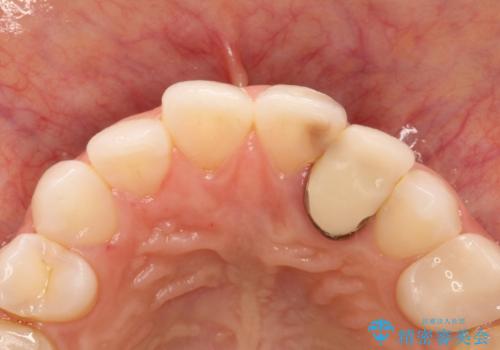

- 以前に被せ物の治療した箇所に汚れが溜まりやすいことを主訴に来院されました。

矯正治療を行なったのち、オールセラミッククラウンにて修復しております。

矯正治療はインビザラインで行なっております。